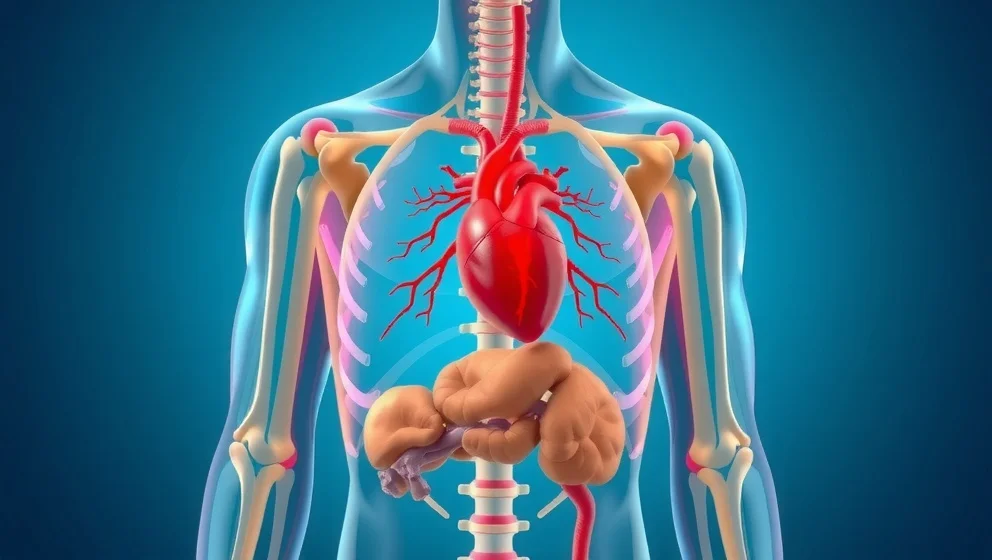

Buken ligger mellan revbenen och bäckenet. Du lär dig var de viktiga organen sitter och hur magen, levern och tarmen fungerar tillsammans.

Hjärtat ligger i bröstet, lite till vänster om mitten. Du lär dig var det sitter, hur stort det är och vad det gör varje dag.

Levern sitter under höger revben och väger ungefär 1,5 kilo. Den är kroppens största inre organ och gör många viktiga jobb för att hålla dig frisk.

Njurarna sitter djupt inne i magen, på varje sida av ryggraden. Du får veta exakt var de ligger och vad de gör.

Hjärtat sitter inte i mitten av bröstet som många tror. Det ligger faktiskt lite åt vänster och är ungefär så stort som din knytnäve.

Blindtarmen sitter i nedre höger delen av magen. Du får veta exakt var den ligger och varför den kan bli inflammerad.